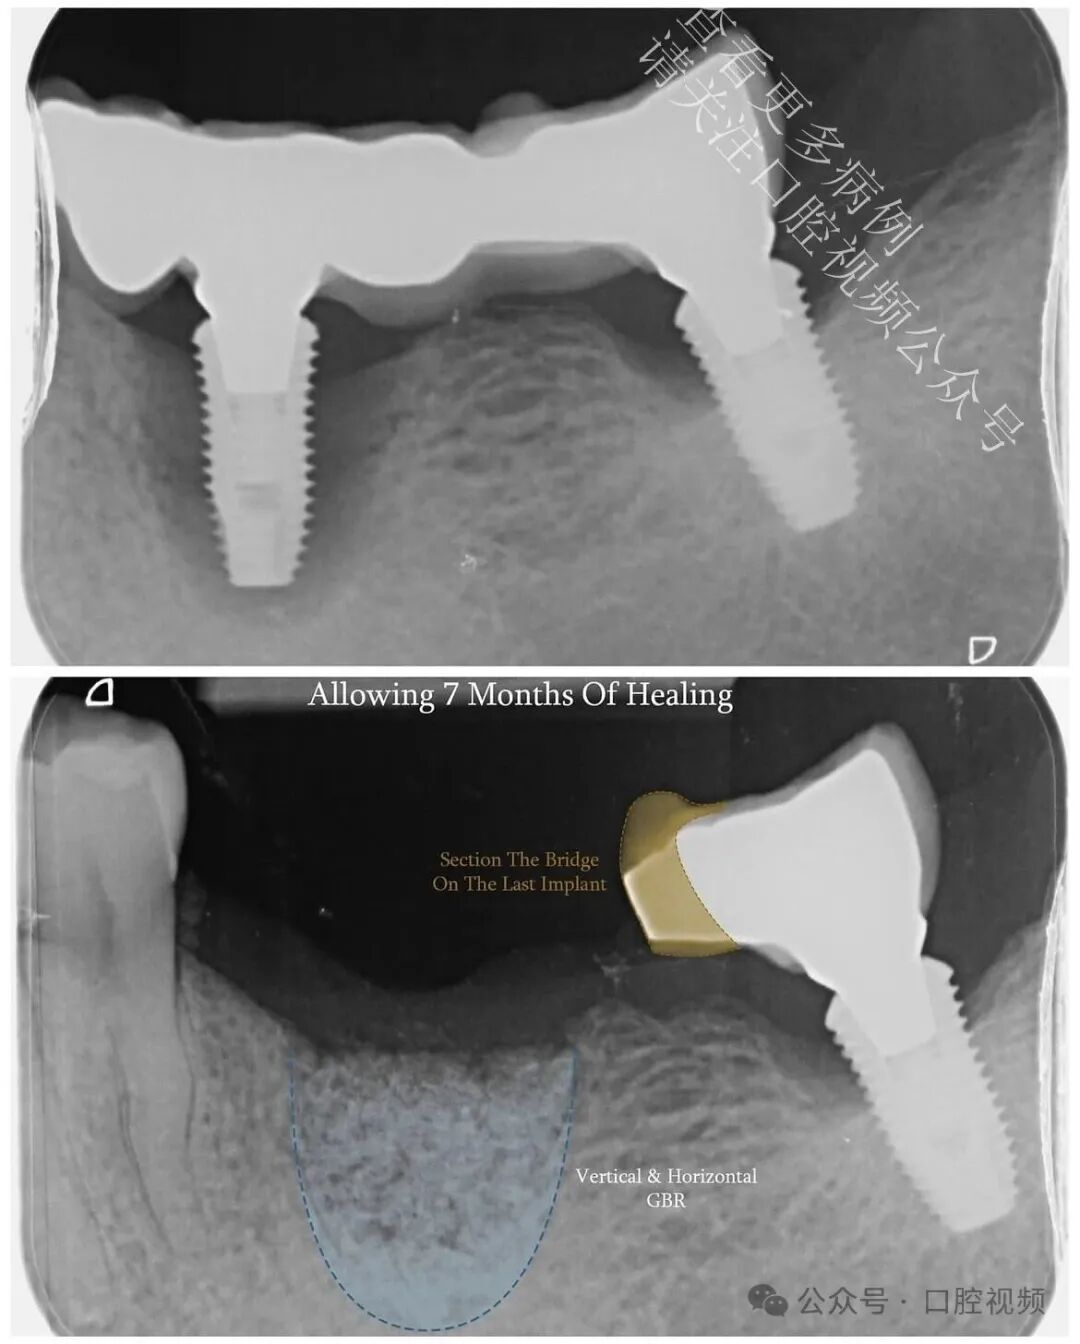

本病例最初计划进行桥体修整,并在近中种植体周围实施垂直+水平向骨增量手术。患者希望保留最后一颗天然牙,因此在等待植骨愈合期间,我将其转诊接受非手术牙周治疗,以稳定软组织。而在愈合过程中,一件令人瞩目的事情发生了:

远中种植体(LL7)开始出现自然的骨增量——此处并未进行任何植骨操作。仅仅是形成了更健康的软组织轮廓、炎症显著减轻,并为生物学自我修复创造了条件。最初,我计划拔除这颗已出现失败迹象的种植体,仅修复 LL5 和 LL6;但鉴于 LL7 周围骨量增加及组织健康状况明显改善,我们最终决定保留并修复该种植体。

在对远中种植体周围实施非手术牙周治疗以稳定软组织后,该种植体开始出现自然的骨增量。未进行任何植骨术,仅通过更健康的轮廓形态、炎症减轻以及为生物学修复留出空间,便实现了这一转变。观察到远中种植体周围骨量增加及组织健康状况改善后,我们决定予以保留。